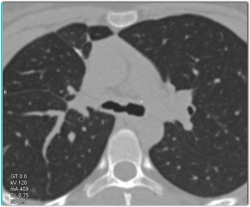

Stenosis of Left Mainstem Bronchus